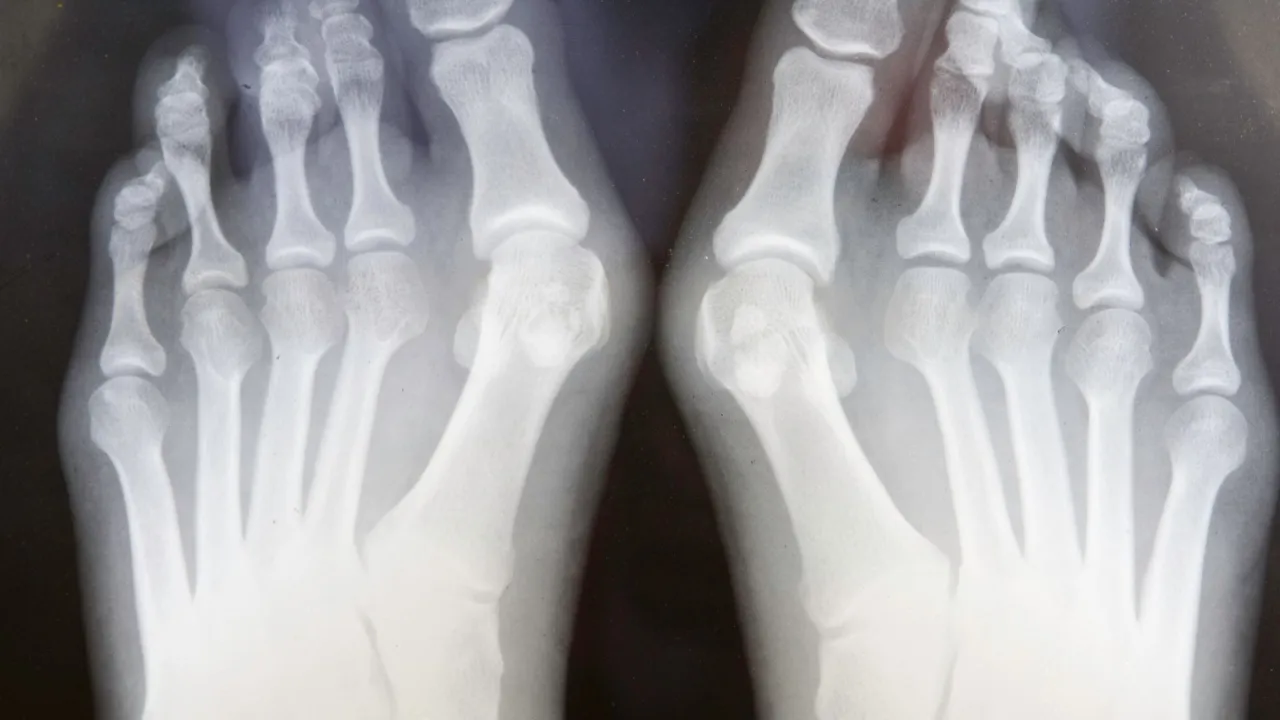

- RTG stopy w obciążeniu: To najważniejsze badanie. Wykonuje się je w pozycji stojącej, co pozwala ocenić stopień deformacji pod naturalnym obciążeniem. Oceniamy kąty koślawości, ustawienie kości śródstopia i palców oraz ewentualne zmiany zwyrodnieniowe.